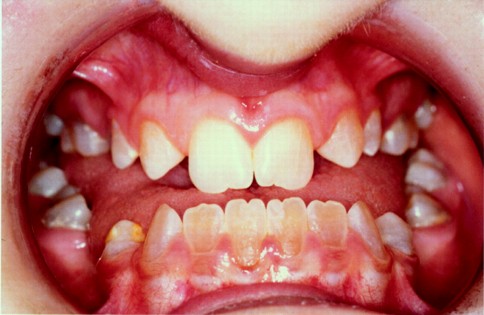

Hyperdontia: the presence of extra (supernumerary) teeth.

Below are examples of mild cases, and examples of extreme cases.

EXTREME CASES

Hyperdontia is the condition of having supernumerary teeth, or teeth that appear in addition to the regular number of teeth. They can appear in any area of the dental arch and can affect any dental organ.

There is evidence of hereditary factors along with some evidence of environmental factors leading to this condition. While a single excess tooth is relatively common, multiple hyperdontia is rare in people with no other associated diseases or syndromes. Many supernumerary teeth never erupt, but they may delay eruption of nearby teeth or cause other dental or orthodontic problems. Molar-type extra teeth are the rarest form. Dental x-rays are often used to diagnose hyperdontia.

The most common supernumerary tooth is a mesiodens, which is a malformed, peg-like tooth that occurs between the maxillary central incisors.